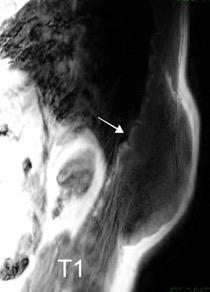

Tumor desmoide (“Fibromatosis agresiva”)

T1: Isointensos con músculos.

T2: Señal intermedia y de alta intensidad.

Presencia frecuente de áreas curvilíneas y lineales dentro de la lesión

Mansour J et al. Diagnostic and Imaging Approaches to Chest Wall Lesions. Radiographics 2022